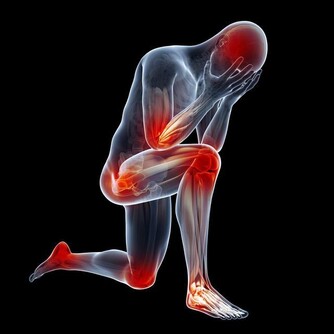

在日常生活和工作中,人們經常會被各種原因導致的“膝蓋”疼所困擾,並逐漸朝著年輕化發展,很多時候,往往因為疼痛程度小,時間段而被人們所忽視,並因此落下“病根”,為以後的生活帶來困擾,今天和大家一起掰扯掰扯那些被你忽略的膝蓋疼到底都是怎麼回事。

哪些常見的損傷會引起“膝蓋”疼?

1.軟組織損傷

軟組織損傷通常指皮膚、皮下、肌肉或是韌帶的損傷,主要原因是由於暴力引起的纖維結締組織撕裂所造成的,這種暴力主要是由於外界暴力或本身運動過度以及熱身不足產生,一旦出現損傷,會伴隨著皮膚、肌肉疼痛,乃至腫脹發生。

2.半月板損傷

半月板是一種彈性軟骨,位於股骨遠端與脛骨平台之間起緩衝作用,防止關節面軟骨受衝擊造成的損傷。半月板損傷主要由於外界暴力引起,也可以由自身退變引起。主要表現為屈伸活動時發生在關節內的彈響或突然“卡住”,多是因為破裂的半月板與脛骨、股骨發生異常的摩擦或嵌頓而產生。

3.膝關節滑膜炎

膝關節是全身關節中滑膜最多的關節,故滑膜炎以膝關節較為多見。膝關節滑膜炎通常指膝部的滑膜受到刺激而引發炎症,進而分泌液失調在關節腔內形成積液的一種病變,包括非特異性滑膜炎和特異性滑膜炎。當關節受外在性和內在性因素影響時,滑膜發生反應,引起充血或水腫,並且滲出液體,表現為關節腫脹、疼痛、關節腔積液、活動受限等。如不及時治療,會影響關節正常活動,並造成關節的破壞甚至病廢。

4.膝關節炎

膝關節炎是一種由膝關節軟骨退行性改變引起的疾病,引起疾病的原因包括年齡、性別、遺傳因素、重複性關節應激和代謝紊亂,病變影響軟骨、軟骨下骨和關節組織,主要特徵為關節軟骨的漸進性破壞與軟骨下骨的硬化,骨贅形成,與滑膜炎有關,臨床症狀表現為劇烈疼痛、關節僵硬、關節活動度顯著降低,有甚者可能進一步導致殘疾發生,嚴重影響患者的生活質量。

除此之外,常見的還有痛風、肥胖、風濕性關節炎以及類風濕性關節炎等都會引起“膝蓋”疼,由此可見,我們需要對此引起高度的重視,做到“早發現,早治療”,防止由於個人忽視導致疾病逐漸加重、惡化,進而對家庭和日常生活產生不良影響。

所以,在日常生活中如果大家碰到”膝蓋疼“,而自己無法斷定病因時,一定要到醫院找專業的醫生做相關的檢查,以免耽誤病情,造成不必要的後果。